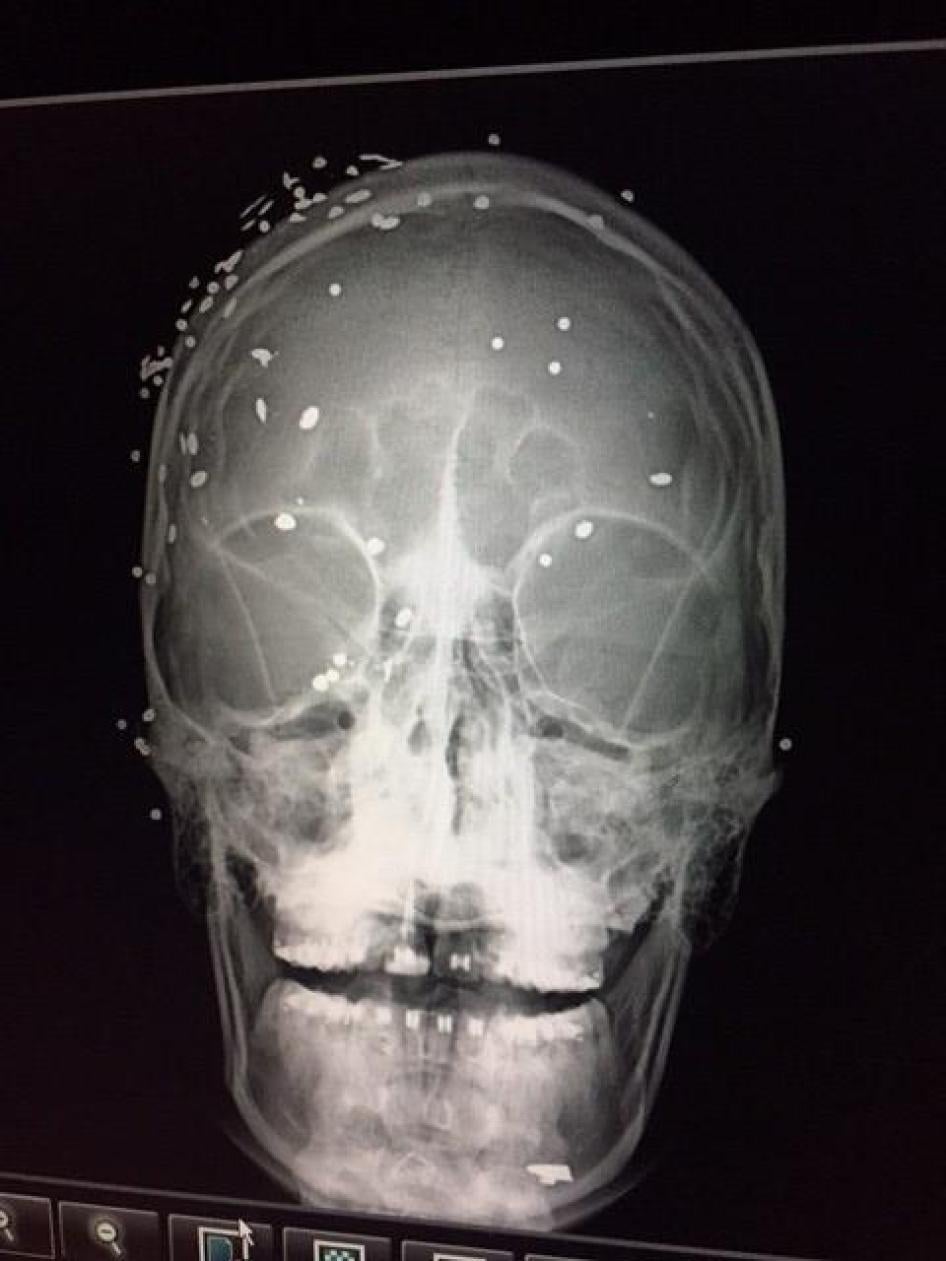

X-ray of patient injured during an anti-government demonstration in Caracas shows many pellet shots to the face and head, June 2017. © 2017 Private